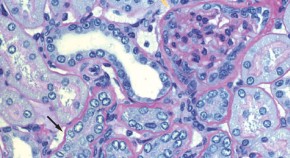

• The Oxford classification of IgA nephropathy identified four histological features with adequate reproducibility and clinical relevance to predict renal outcome in patients with IgA nephropathy. Does the predictive value of biopsy lesions apply across a range of patient ages?